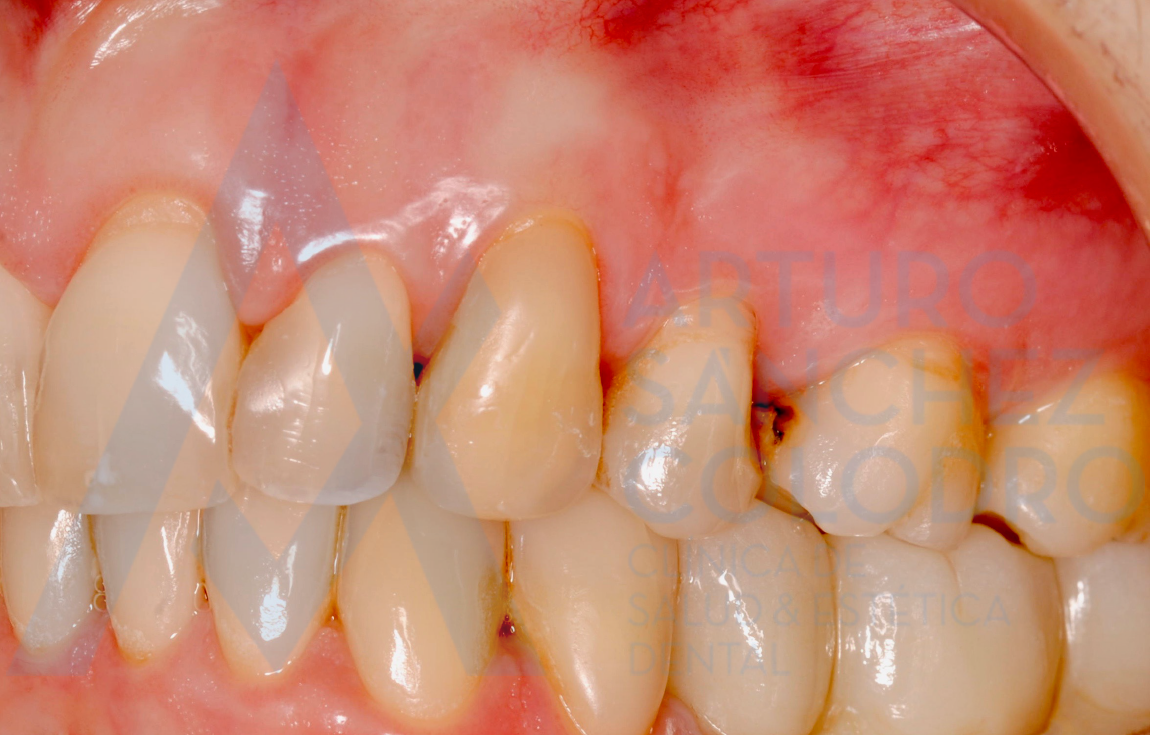

Los tecnicismos puede que no os digan mucho, pero dejamos por aquí unas fotos del antes y el después en las que puede apreciarse la mejoría del caso:

(cirugía)